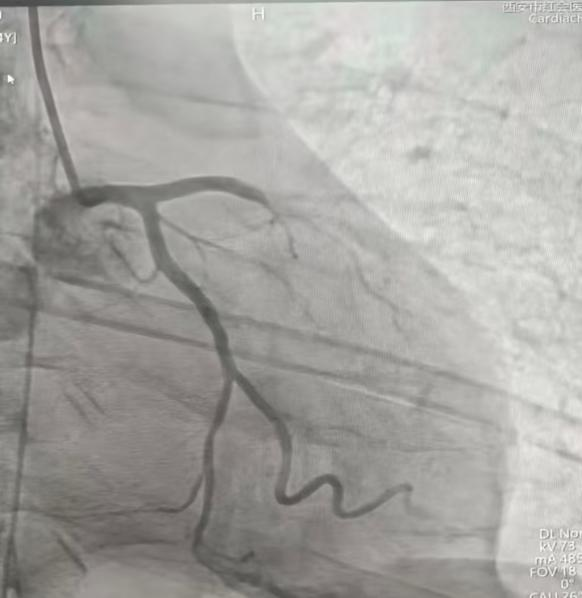

术中造影清晰地揭示了病变本质:前降支(LAD)近、中段100%闭塞——这是导致广泛前壁心梗、心源性休克、心脏骤停的“罪魁祸首”。其他血管也存在不同程度的狭窄。

李超民主任团队精准操作:导丝通过闭塞段,球囊预扩张,随后精确植入一枚药物洗脱支架。术后造影显示:前降支血管狭窄完全消失,血流通畅。他们用极短的时间,重新打开了患者生命的“主干道”。

介入治疗前冠脉造影